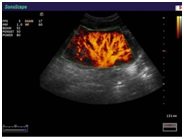

В Медицинском центре «АКВА МЕД МАРИН» проводится УЗИ-диагностика на новейшем ультразвуковом диагностическом сканере Экспертного класса SonoScape S40Exp, в том числе и УЗИ детям с применением специальных детских датчиков. Цветной допплер помогает точной диагностике патологии сосудов и сердца у детей.

- Педиатрия - Неонатология - Нейросонография - Сосуды |

Компания SonoScape уделила особое внимание допплеровским режимам и является экспертом в своем классе, что позволяет с легкостью, но в то же время с уникальной точностью проводить исследования с постановкой наиболее точного диагноза.

Ультразвуковые исследования, доплеровское сканирование сосудов в Медицинском центре «АКВА МЕД МАРИН» выполняется при помощи аппарата SonoScape S40Exp (экспертного класса, который оснащен множеством новейших функций, многократно улучшающих качество и информативность УЗИ-исследования).